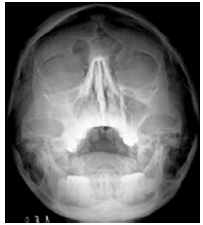

Analise as radiografias da face abaixo e marque a alternativa que contém o nome das incidências correspondentes.

01 -

02 -